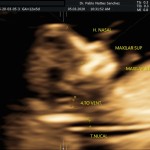

- Los Marcadores Cromosómicos y determinación de riesgo para trisomías (Rastreo de S. Down y otros con una sensibilidad del 85 a 90%).